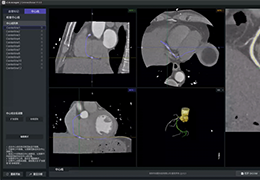

工作流智能。

在这里,先进的智能功能自动执行手动任务和工作流程步骤,以简化流程,提高技术人员工作效率,节省时间和金钱,并增强患者护理。

自动化设备定位和患者姿势确认可优化放射科技师的效率并加快工作流程。

自动技术选择可改善影像一致性并支持辐射剂量控制。

通过任务自动化功能改进感染控制,使放射科技师不再与潜在感染患者直接接触。